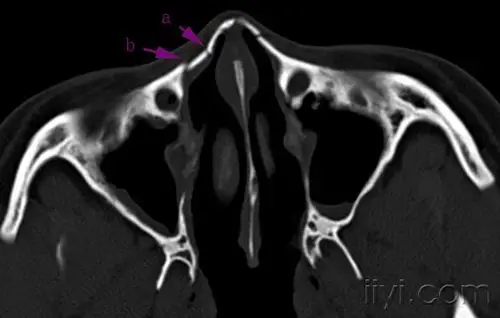

教科书式的鼻骨骨折!dr ct!